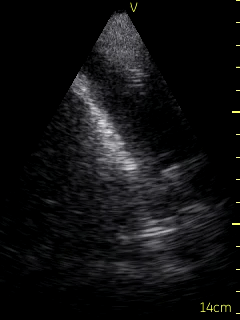

Ultrasound of the lung bases was conducted to assess for effusion by the consultant Respirologist using a Vscan device. There was no fluid present in the patient’s right pleural space. A moderate sized pleural effusion (Figure 1) was seen on the left side. The ultrasound of the left lung based was used to guide the thoracentesis (Video 1). The site of catheter insertion was landmarked at the 8th intercostal space, roughly 10 cm from the spine. Lidocaine was used to anesthetize down to the pleura. The catheter was introduced along the same location and angle, and a total 1.5 litres of serosanguinous fluid was collected. The procedure was well tolerated without complications.  Ultrasound following the procedure showed a very small amount of remaining fluid. Sliding lung/pleura could be seen as well. The patient experienced relief of symptoms following the procedure.